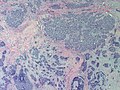

Adenoid cystic carcinoma of the breast

Adenoid cystic carcinoma of the breast. H&E stain. | |

Adenoid cystic carcinoma of the breast is a rare type of breast cancer that is similar to a relatively common tumour of the salivary gland.

Microscopic